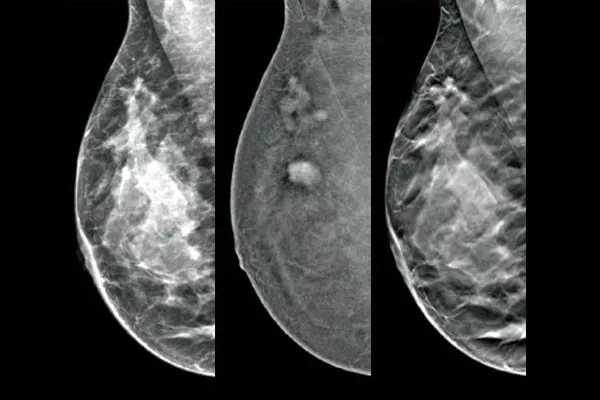

Target and biopsy lesions identified with 2D contrast-enhanced mammography through a stereotactic-based procedure, with a comparable diagnostic performance to a breast MRI procedure.1,2 Compare post-marker images in the same modality as the initial diagnostic contrast exam.

Affirm Contrast Biopsy software allows you to biopsy lesions identified during the I-View™ contrast-enhanced 2D mammogram. By leveraging the ability to provide 2D, contrast-enhanced, and tomosynthesis images under one compression,4 The Affirm Upright Breast Biopsy Guidance System enables a quick transition from screening to biopsy, leveraging the same proven imaging chain5 as the mammography system to improve 3D™ visualisation of suspicious lesions.**

Functional imaging, using CEM, compares favourably to breast MRI with similar sensitivity, higher specificity, and higher positive predictive value.7,8 In addition, CEM provides a cost-effective diagnostic imaging alternative9 compared to MRI, with a shorter procedural time.7,10